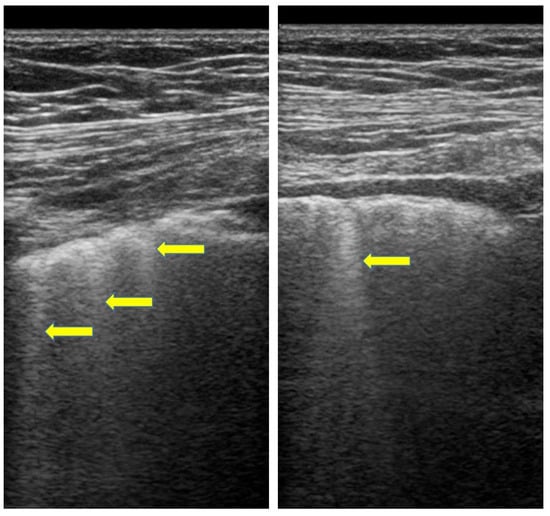

- Gasperini, M.L.; Gigante, A.; Iacolare, A.; Pellicano, C.; Lucci, S.; Rosato, E. The predictive role of lung ultrasound in progression of scleroderma interstitial lung disease. Clin. Rheumatol. 2020, 39, 119–123. [Google Scholar] [CrossRef]

- Bruni, C.; Mattolini, L.; Tofani, L.; Gargani, L.; Landini, N.; Roma, N.; Lepri, G.; Orlandi, M.; Guiducci, S.; Bellando-Randone, S.; et al. Lung Ultrasound B-Lines in the Evaluation of the Extent of Interstitial Lung Disease in Systemic Sclerosis. Diagnostics 2022, 12, 1696. [Google Scholar] [CrossRef]